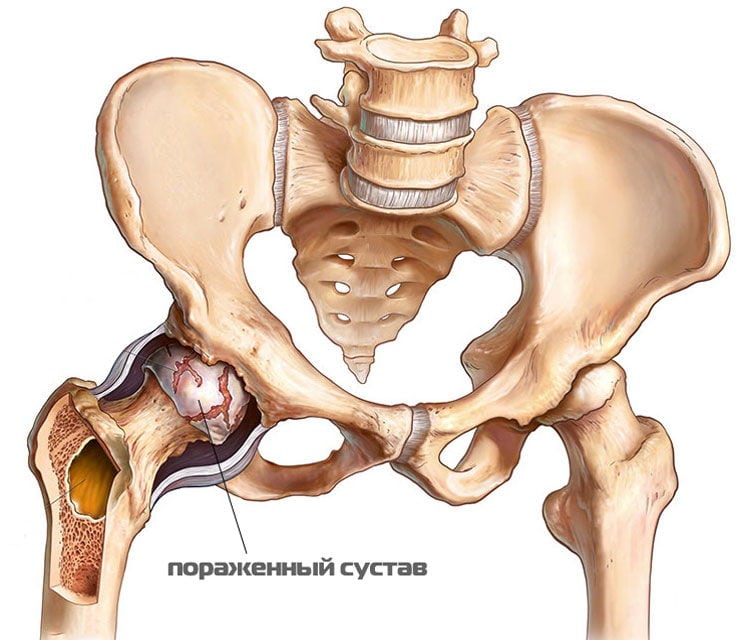

- асептический некроз костной головки — отмирание тканей в тех участках, где на тазобедренный сустав ложится наибольшая нагрузка. Симптоматика патологии проявляется так: на начальном этапе боль в правом или левом бедре резкая, внезапная, локализующаяся в области сустава. Затем она распространяется в пах, пояснично-крестцовый отдел позвоночника, колено. В течение нескольких дней интенсивность болевого синдрома не снижается, мешая человеку не только передвигаться, но и сидеть. Затем самочувствие человека улучшается, дискомфортные ощущения возникают лишь при серьезных физических нагрузках. Вскоре они возвращаются, а их выраженность значительно усиливается.